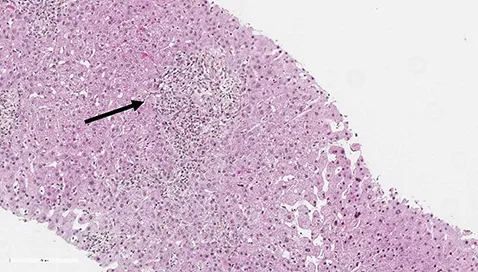

Les patients suivis pour une CBP peuvent présenter des degrés variables d’inflammation hépatique mais habituellement, dans la CBP, on retrouve très peu d’hépatite d’interface ou d’hépatite lobulaire. Environ 8 à 10 % des patients CBP vont présenter des lésions hépatiques faisant évoquer une HAI associée (1, 2). Le syndrome de chevauchement CBP+ HAI peut être présent d’emblée dès le diagnostic initial de la CBP dans 60 % des cas mais les patients CBP peuvent également, dans 30 % des cas, présenter une HAI dite secondaire apparaissant parfois plusieurs années après le diagnostic. Les patients HAI peuvent présenter dans 10 % des cas une CBP dite secondaire (figure 1) (3). Dans le cadre d’une CBP, une augmentation anormalement élevée des transaminases (> 5N) et des IgG (> 20 g/l) doit faire suspecter une HAI associée (4). Des anticorps anti- muscle lisse de spécificité anti-actine et des anticorps anti-ADN double-brin peuvent être présents dans 10 % des cas de CBP. Leur présence doit également faire suspecter l’existence d’un syndrome de chevauchement CBP+ HAI. Dans une étude s’intéressant aux anticorps anti-ADN double brin, ceux-ci étaient présents chez 60 % des patients CBP+ HAI, mais seulement chez 4 % des patients CBP et 26 % des patients HAI (p<0,0001 et 0,01 respectivement). La double positivité d’anticorps anti-ADN double brin et d’anticorps anti-mitochondries était présente chez 47 % des patients CBP+ HAI, mais seulement chez 2 % des pathologies contrôles (5). Dans une autre étude, la présence d’anticorps anti-ADN double brin, une augmentation des ALAT et des IgG étaient les trois facteurs significativement associés aux CBP+ HAI (6). De plus, chez les patients CBP non répondeurs à 12 mois à l’acide ursodésoxycholique (AUDC), une HAI doit être systématiquement recherchée. La présence d’un seul élément évocateur d’HAI n’est en revanche pas suffisant pour poser le diagnostic de syndrome de chevauchement. La réalisation d’une biopsie hépatique, en l’absence de contre-indication, est nécessaire pour confirmer le diagnostic de CBP+ HAI. La présence d’une hépatite d’interface et/ou d’une hépatite lobulaire, bien que non spécifiques, et son intensité permet de confirmer la présence d’une HAI. Le score histologique « modified HAI » (mHAI) développé par Ishak et al. permet de décrire l’activité hépatique inflammatoire et définit les indications de traitement (7, 8). Ce score décrit 4 catégories d’inflammation nécrotico-inflammatoire : l’hépatite d’interface périportale, la nécrose confluente, l’inflammation lobulaire et l’inflammation portale (figure 2). Un score mHAI> 4 est une indication de traitement immunosuppresseur. Les critères de Paris définis par Chazouillières et al. sont cependant les plus couramment utilisés et recommandés par la société européenne pour l’étude du foie (EASL) pour poser le diagnostic de syndrome de chevauchement CBP+ HAI. Ils reposent sur la présence d’au moins deux critères sur trois de CBP : PAL> 2N ou GGT> 5N ; anticorps anti mitochondries≥ 1/40 ; lésions biliaires florides à l’histologie et d’au moins deux critères sur trois d’HAI : ALAT> 5N ; IgG sériques> 2N ou présence d’anticorps anti muscle lisse ; une hépatite d’interface modérée à sévère en histologie (tableau 2, figure 2) (1). Dans une étude publiée en 2010, la sensibilité et la spécificité des critères de Paris pour diagnostiquer une CBP+ HAI étaient respectivement de 92 % et 97 % (9). Le score de Paris est un score différent de ceux utilisés pour faire le diagnostic de chaque pathologie propre CBP ou HAI. Le groupe de travail international de l’HAI ne recommande pas l’utilisation des scores diagnostiques habituels d’HAI (corrigés ou simplifiés) pour faire le diagnostic de CBP+ HAI du fait de leurs très faibles sensibilité et spécificité (9-12). L’objectif de poser un diagnostic de syndrome de chevauchement, et de manière précoce, est de pouvoir proposer un traitement adapté, notamment immunosuppresseur afin d’éviter la progression de la fibrose. Néanmoins, il est important de ne pas porter de diagnostic par excès afin d’éviter aux patients des effets secondaires d’une corticothérapie et/ou d’un traitement immunosuppresseur qui peuvent être sévères.

Figure 2 : Lésions histologiques biliaires évocatrices de CBP (A, B, C), lésions histologiques d’hépatite d’interface et d’hépatite lobulaire évocatrices d’HAI (D, E, F).